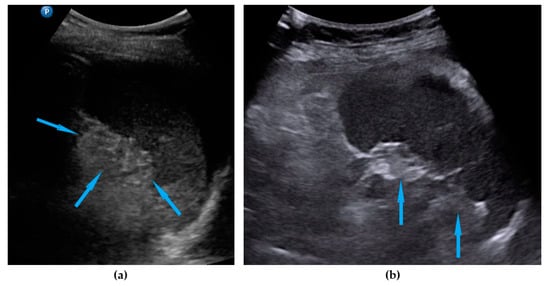

| Omentum | Focal infiltration of omentum: hypoechogenic nodules with discrete vascularization. Diffuse infiltration: omental cake appears as a nodular, perfuse, and non-peristaltic tumor that is located between the anterior abdominal wall and bowel loops. | Figure 1 | Video S1 |

| Small bowel mesentery root | Involvement is suspected when bowel loops have poor mobility and are “fixed together” in the dynamic ultrasound examination with a cauliflower-like image. | Figure 2 | Video S2 |